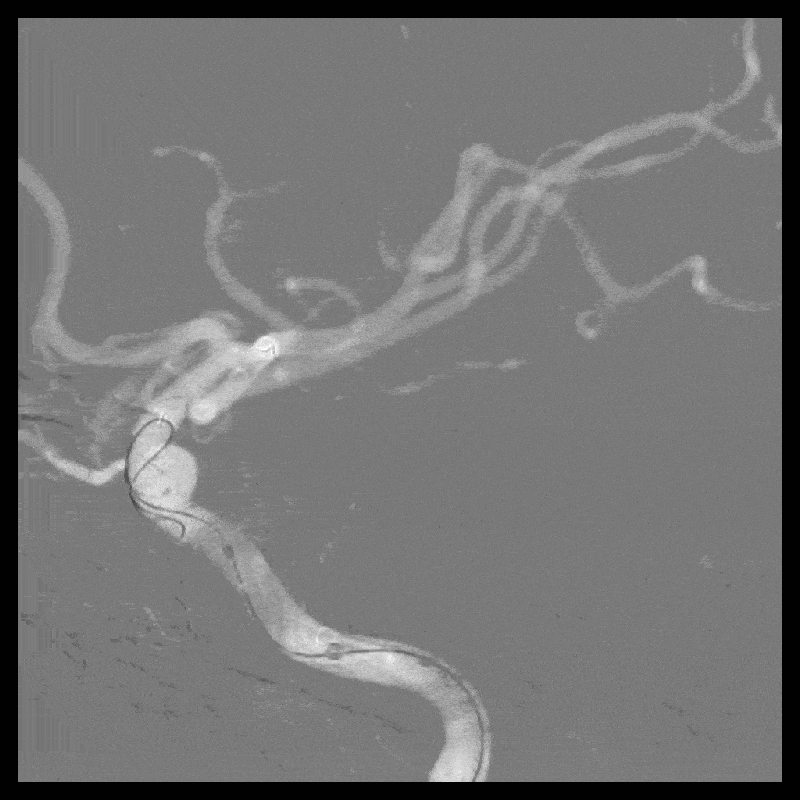

2022-2-21 右侧颈内动脉血流导向装置重建术(Tubridge)

R-ICA血流导向装置(Tubridge3.5*20mm)

14:30 患者诉轻度头痛。

神清语利,肢体活动正常。

15:10 停用替罗非班,急查头颅CT。

少量出血(SAH?实质?),无神经功能受损。

停用波立维,继续吲哚布芬0.1g 2/日。